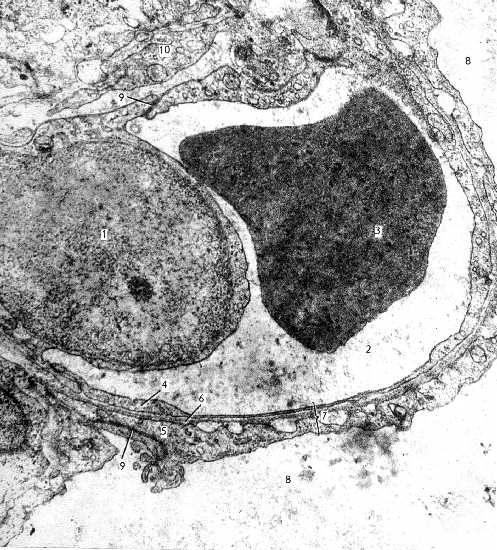

II. Ещё одна иллюстрация барьера

| Электронная микрофотография. Лёгкое: аэрогематический барьер. | |

На этом снимке - несколько иной ракурс. а) Основную часть кадра занимает кровеносный капилляр, где 1 - ядросодержащая часть одного из эпителиоцитов, выбухающая в просвет (2) капилляра; 3 - эритроцит. б) Просвет альвеолы - 8; сурфактант на снимке отсутствует. в) Остальные компоненты барьера - налицо: тонкие цитоплазматические части (5) альвеолоцитов I типа, соединённых между собой десмосомами (9), слившиеся базальные мембраны (6) эпителия и эндотелия, тонкие цитоплазматические части (4) эндотелиоцитов, тоже соединённых между собой десмосомами (9) (вверху снимка) | |

| г) Ещё выше на снимке виден фрагмент (10) неэпителиальной клетки. Это может быть адвентициальная клетка капилляра или какая-либо иная клетка - например, липофибробласт. |